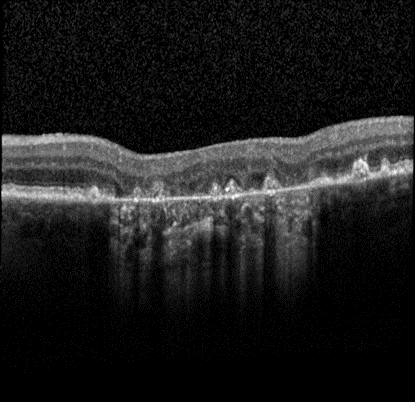

Advanced form of age-related macular degeneration (AMD) is a major health burden that can lead to irreversible vision loss in the elderly population. For early preventative interventions, there is a lack of effective tools to predict the prognosis outcome of advanced AMD because of the similar visual appearance of retinal image scans in the early stage and the variability of prognosis paths among patients. An early characteristic of AMD is drusen, which appears as yellowish deposits under the retina (Figure 1 left). AMD is mainly categorized into two types: Dry AMD (non-neovascular, Figure 1 middle) is represented by drusen deposition, later evolving into confluent areas of regressed drusen and ultimately in the advanced dry stage presenting as loss of vision associated with retinal pigment epithelium (RPE) atrophy (clinically known as geographic atrophy, GA). Wet AMD (neovascular, Figure 1 right) is characterized by the leakage of fluid in the sub-RPE and subretinal spaces caused by neovascularization. The overall objective for this study is to design, develop, and evaluate AMD prognosis prediction models that can detect most relevant images containing AMD biomarkers, manage unevenly spaced sequential optical coherence tomography (OCT) images and predict all advanced AMD forms that can help with the interpretation and explainability of computer-aided prognosis models. Read more

Figure 1: Dursen (left), Dry AMD (middle) and Wet AMD (right)